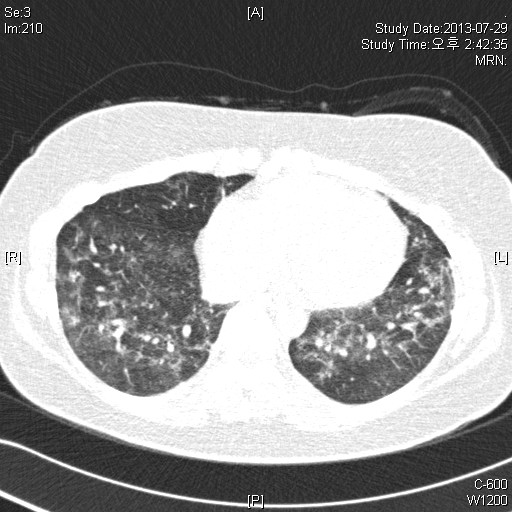

39¿©ÀÚ È¯ÀÚ·Î, Rt breast cancer Áø´ÜÇÏ¿¡ 2013³â 3¿ùºÎÅÍ Ç×¾Ï Ä¡·á ¹ÞÀº ȯÀÚ·Î,

dyspnea on exertion ¾ÇÈ­µÇ¾î È£Èí±â³»°ú ¹æ¹®ÇÔ.

CRP 0.68 mg/l, Procalcitonin<0.05 mg/dl

CBC: 6000-12.1-246k(neutrophil:71.8%, eosinophil 1.0%)

PFT: FVC/FEV1/Ratio: 2140(56%)/ 1810(60%)/ 84% (3ÃÊ ÀÌ»ó ºÒÁö ¸øÇÔ)

Bronchodialtor response (-)